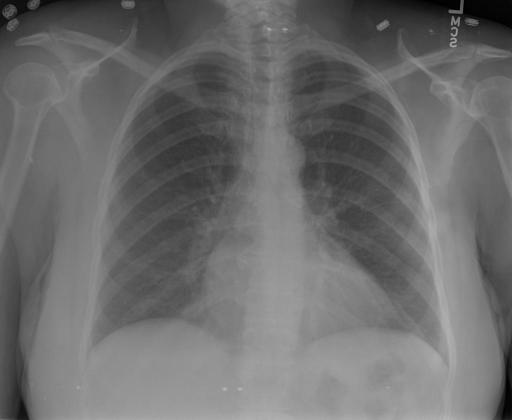

- (1)准备[诊疗报告(中文)](./data/Xray/openi-zh.json)和[X光影像](https://pan.baidu.com/s/13GBsDMKf6xBZBSHpoWH_EA?pwd=k9sh)在`data/Xray`文件夹下; - (2)开始训练: ```bash # 设置CUDA变量,主要是为了解决有时候直接训练而出现无法正确加载到显卡问题 export CUDA_VISIBLE_DEVICES=0,1,2,3 # 开始训练 bash finetune_XrayGLM.sh ``` 这里的复现过程非常简单,主要是很多过程我们都为大家准备好了,大家可以随时复现一个自己的`XrayGLM`。 ### 4.模型训练(通用) ## 效果展示 *以下效果来自于**低质量**的数据训练和权重 影像诊断: |X光影像|诊疗报告(医生)|XrayGLM| |:-|:-|:-| |![](./data/Xray/2_1.png)|根据X射线图像,心脏大小正常,肺部看起来很清晰。已经排除了肺炎、积液、水肿、气胸、腺病、结节或肿块的存在。该发现表明一切正常。换句话说,总体印象是胸部正常。|X光片显示,心脏大小正常。肺部没有气胸或胸腔积液的证据。骨骼结构看起来没有任何异常。总的来说,X光片表明没有发现急性心肺疾病的迹象。| |![](./data/Xray/2882_1.png)|X光图片显示没有扭曲的区域、可疑的骨质不透明度或胸腺积液。心脏大小轻微增大,但非常稳定。此外,没有气胸的证据,肺野也正常。总体来说,X光片显示没有急性心脏异常,但要注意轻微的心脏扩大。|X光片显示,心脏大小正常。肺部和纵隔轮廓清晰,没有气胸或胸腔积液的证据。骨骼结构完整,没有任何急性异常。| |![](./data/Xray/2577_1.png)|心影形态在正常范围内。没有急性骨质异常。有可能出现没有明显的吸水或肺实质状况的线索。没有大面积积液或气胸。有可能怀疑其有误吸或肺实质问题。为了确诊和治疗,可能需要进行适当的影像学随访。|心脏大小正常,肺部和纵隔轮廓清晰。没有急性异常或活动受限的证据。没有任何明显的气胸、胸腔积液或肺不张的迹象。此外,也没有发现任何局灶性骨质异常或其他急性疾病。| 多轮对话: |X光影像|诊疗报告(医生)| |:-|:-| |![](./data/Xray/861_1.png)|右侧主动脉突出观察到。心脏大小正常。胸部未发现明显的肺气肿、胸膜积液或可疑的肺部病变。报告指出已知右侧主动脉情况正常。| ```bash >> X光影像路径:./data/Xray/861_1.png >> 用户:这是一张什么图? >> XrayGLM:这张图片显示的是一张肺部检查的X光片。 >> 用户:请描述这张胸部X光片的诊断结果 >> XrayGLM:心脏大小正常,肺部清晰。没有急性心肺疾病的证据。 >> 用户:是否存在肺气肿? >> XrayGLM:没有肺气肿。心脏大小正常,肺部清晰。没有发现急性心肺疾病的证据。 >> 用户:平时饮食该注意什么? >> XrayGLM:饮食应该健康,均衡。建议增加蛋白质的摄入量,因为蛋白质有助于维持肌肉和骨骼的健康。多食用蔬菜、水果、全谷物以及健康的脂肪来源如橄榄油、鱼类等可以帮助获得足够的维生素和矿物质。此外,避免过度饮酒或吸烟,这些习惯可能会对心脏健康产生负面影响。 ``` ## 未来展望 1. 模型的能力更多来源于数据的支持,`OpenI-zh`作为微调数据集,其数据量足以支持研究,在更广泛的任务和性能表现上,我们认为**在大规模数据集上预训练并在高质量少量数据集上微调是一种可行的方案**; 2. 普遍意义的理解上,视觉多模态模型=视觉模型+语言模型。除了需要关注视觉模型信息与语言模型输出的搭配外,还需要**额外关注到语言模型的加强,在人机的对话中,尤其是医疗语言模型的问答上,除了专业的医疗问题回答,带有人文情怀的有温度的回答更应该是我们追寻的目标**。 3. **高精度的模型永远打不过大参数的模型**,如果在6B模型和13B模型上选择微调,请在资源充足情况下选择13B的大参数模型; ## 项目致谢 1. [VisualGLM-6B](https://github.com/THUDM/VisualGLM-6B)为我们提供了基础的代码参考和实现; 2. [MiniGPT-4](https://github.com/Vision-CAIR/MiniGPT-4)为我们这个项目提供了研发思路; 3. ChatGPT生成了高质量的中文版X光检查报告以支持XrayGLM训练; 4. [gpt_academic](https://github.com/binary-husky/gpt_academic)为文档翻译提供了多线程加速; 5. [MedCLIP](https://github.com/RyanWangZf/MedCLIP) 、[BLIP2](https://huggingface.co/docs/transformers/main/model_doc/blip-2) 、[XrayGPT](https://github.com/mbzuai-oryx/XrayGPT) 等工作也有重大的参考意义; ![](./assets/images/mpu.png) 这项工作由[澳门理工大学应用科学学院](https://www.mpu.edu.mo/esca/zh/index.php)硕士生[王荣胜](https://github.com/WangRongsheng) 、[段耀菲](https://github.com/IsBaSO4) 、[李俊蓉](https://github.com/lijunrong0815)完成,指导老师为檀韬副教授、[彭祥佑](http://www.patrickpang.net/)老师。 *特别鸣谢:[USTC-PhD Yongle Luo](https://github.com/kaixindelele) 提供了有3000美金的OpenAI账号,帮助我们完成大量的X光报告翻译工作 ## 免责声明 本项目相关资源仅供学术研究之用,严禁用于商业用途。使用涉及第三方代码的部分时,请严格遵循相应的开源协议。模型生成的内容受模型计算、随机性和量化精度损失等因素影响,本项目无法对其准确性作出保证。即使本项目模型输出符合医学事实,也不能被用作实际医学诊断的依据。对于模型输出的任何内容,本项目不承担任何法律责任,亦不对因使用相关资源和输出结果而可能产生的任何损失承担责任。 ## 项目引用 如果你使用了本项目的模型,数据或者代码,请声明引用: ```bash @misc{wang2023XrayGLM, title={XrayGLM: The first Chinese Medical Multimodal Model that Chest Radiographs Summarization}, author={Rongsheng Wang, Yaofei Duan, Junrong Li, Patrick Pang and Tao Tan}, year={2023}, publisher = {GitHub}, journal = {GitHub repository}, howpublished = {\url{https://github.com/WangRongsheng/XrayGLM}}, } ``` ## 使用许可 此存储库遵循[CC BY-NC-SA](https://creativecommons.org/licenses/by-nc-sa/4.0/) ,请参阅许可条款。